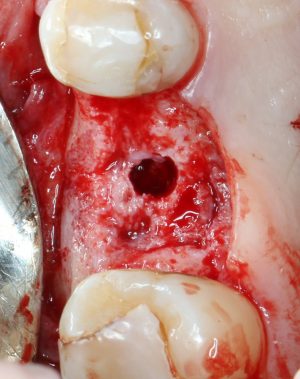

Пришло время вернуться к синуслифтингу и заполнить сформированное ранее субантральное пространство графтом (Geistlich Bio-Oss Pen):

запечатываем заполненное субантральное пространство:

Приступаем к установке имплантата.

Если лунка подготовлена правильно, то имплантат проваливается в неё почти полностью:

и докручивается до правильного положения несколькими оборотами.